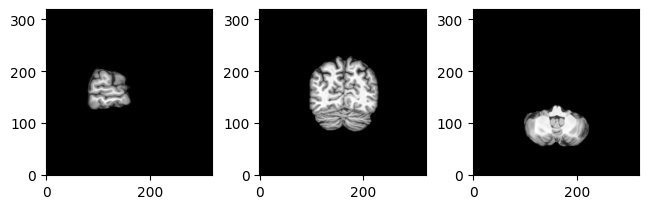

MriSlicer

slices the MRI image. SlicesPlotter

takes care of plotting slices. By default, it plots side, front and top views.

slices_plotter.plot(slicer.slice(img_fdata, (35, 70, 105)));

For convenience, there’s also MriPlotter